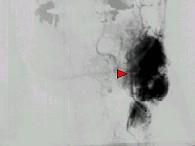

问题 50岁女性,颈部无痛性肿块,逐渐增大,听诊可闻及杂音,DSA检查如图所示,请选择最可能诊断 ( )

选项 A、颈动脉硬化 B、动静脉瘘 C、假性动脉瘤 D、颈动脉夹层 E、颈动脉体瘤

答案 E